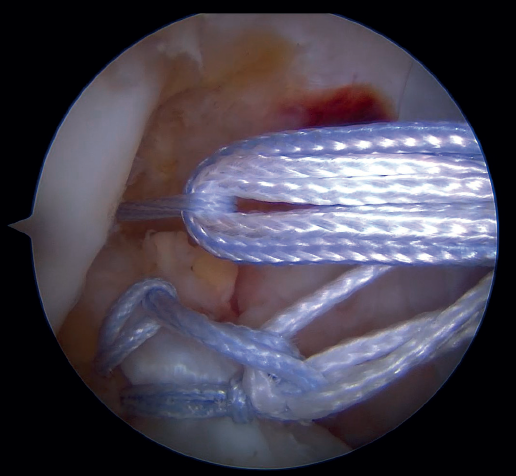

Our attention now turns to outside the knee, where the loop of the cortical suspension system (ACL Repair TightRope®) is secured to the ACL using the FiberRing® sutures. This device is a cortical suspension button with a loop of variable length, which also incorporates a high strength tape. To secure it, the suture marked as "1" on the card is first passed through the retriever thread of one of the FiberRing® sutures, and then the step is repeated through the retriever thread of the remaining FiberRing® suture. Next, this thread passing through the rings of the FiberRing® system is passed through the closed loop marked as "2". Finally, this thread is passed through the nitinol marked "3"; the card is held firmly and the nitinol is pulled so that the TightRope® thread passes through the cortical plate. At this point, part of the loop, the button and the threads connected to it (loop traction sutures, button lift sutures and high strength tape) remain outside the knee, waiting to be inserted into the joint (Figure 8).

The next step is to remove the femoral retriever thread through the cannula of the anteromedial portal, loading it with the traction and flipping sutures, but not with the high strength tape. By pulling on the retriever thread, the ACL RepairTightRope® sutures will pass through the femoral tunnel (Figure 9), exiting through the skin. Using the lift sutures, the button is then likewise advanced through the tunnel until it is flipped over the lateral femoral cortex (which can be checked by pulling firmly on the high strength tape, which still exits through the cannula). At this point, all that remains is to pull alternately on both loop traction sutures to shorten the loop and reduce the stump of the ACL until contact is made with its native footprint.